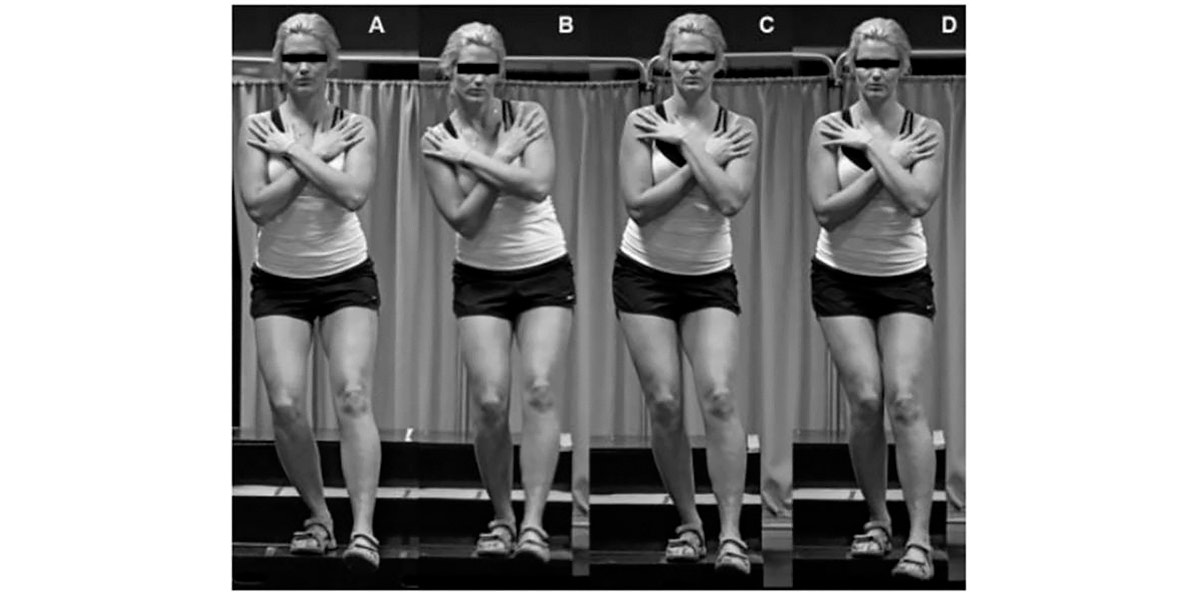

Para isso, deves realizar um teste de pistol squat excêntrico e gravar-te de frente.

Figura XIII. Diferentes modelos graduados A-D segundo a disfuncionalidade apresentada num teste de agachamento unilateral excêntrico para o diagnóstico da causa do joelho de corredor.

- Se o teu movimento for semelhante a A, bom sinal;

- Se for semelhante a B, deves fortalecer o core, és instável, amigo/a…;

- Se for semelhante a C a tua anca falha, tens fraqueza nos músculos pelvitrocantéreos, e deves trabalhá-los da forma que indiquei anteriormente;

- E se fores semelhante a D… estás muito mal, uma vez que apresentas uma perda de controlo sobre o joelho, anca e eversão do pé.